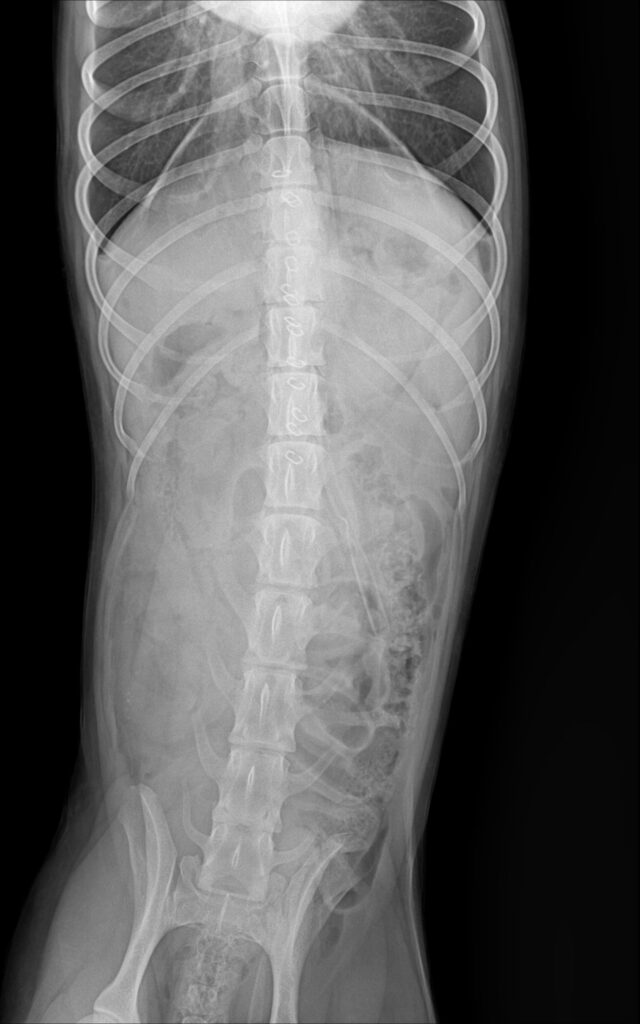

수술 전 방사선 사진 / 출처: 미래동물의료센터

엑스레이 검사에서 위 내부에 밝은 음영의 물질이 확인되었으며, 형태와 밀도로 보아 돌 이물로 강하게 의심되는 소견이었습니다.이물의 크기와 위치상 자연 배출이나 구토 유도만으로는 제거가 어렵다고 판단되어 위절개 수술을 통한 이물 제거가 필요하다고 설명드렸습니다.